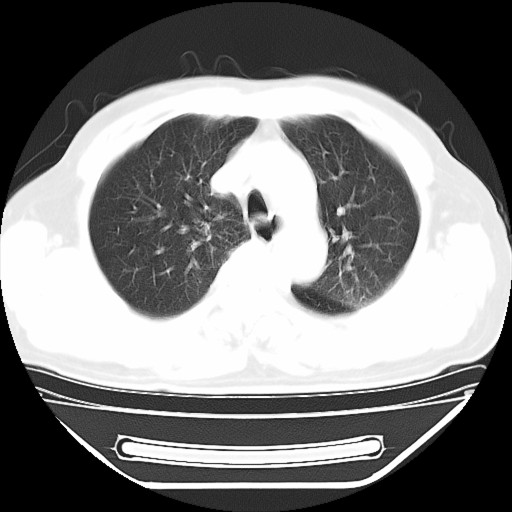

以下是引用hhcckk在2009-5-29 10:34:00的发言:[br]左下肺片絮状边缘模糊影,考虑感染,建议治疗后复查[br]